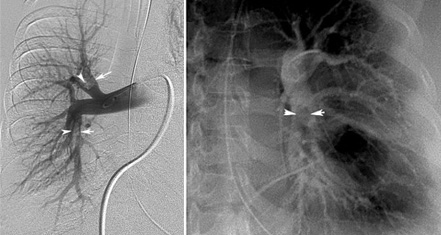

Pulmonary Angiogram

(On left) Intraluminal defects in the right lower lobe and lower lobe branches of pulmonary artery.

(On right) Intraluminal filling defect left lower lobe branch of pulmonary artery.